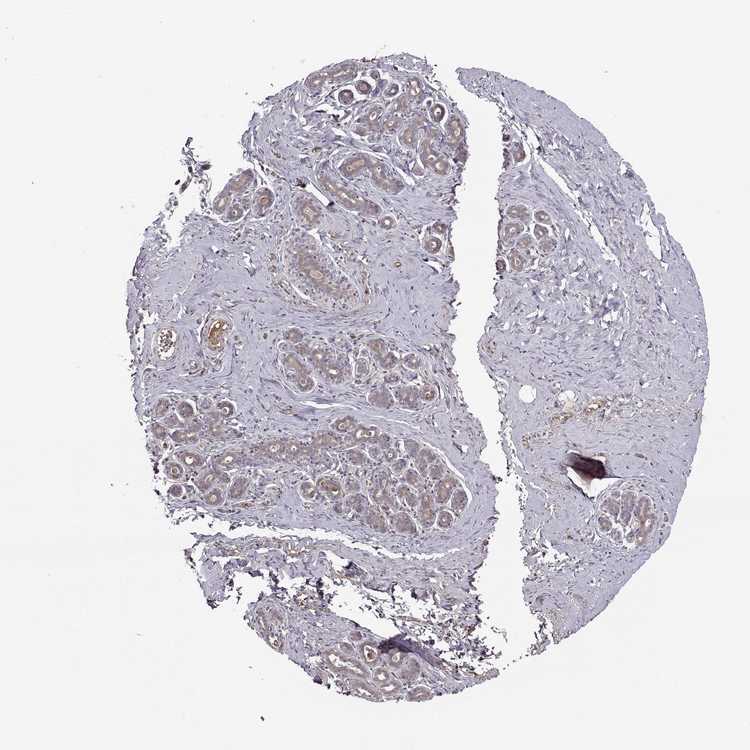

BREAST - Antibody stainingi

Antibody staining in the annotated cell types in the current human tissue is reported as not detected, low, medium, or high, based on conventional immunohistochemistry profiling in selected tissues. This score is based on the combination of the staining intensity and fraction of stained cells.

Each image is clickable and will lead to virtual microscopy that enables deeper exploration of all samples and also displays staining intensity scores, fraction scores and subcellular localization as well as patient and tissue information for each sample.

Antibody HPA070759

Adipocytes Not detected

Glandular cells Low

Myoepithelial cells Not detected